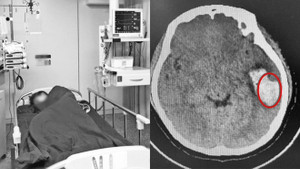

Bị phình mạch máu não, người đàn ông ở Hà Nội đau đầu suốt 2 tuần, uống thuốc nhưng không khỏi.

Đang hát karaoke, Hoan Hoan bỗng thấy chóng mặt, buồn nôn, sau khi khám, bác sĩ cho biết cô bị vỡ mạch máu não, cần mổ cấp cứu.